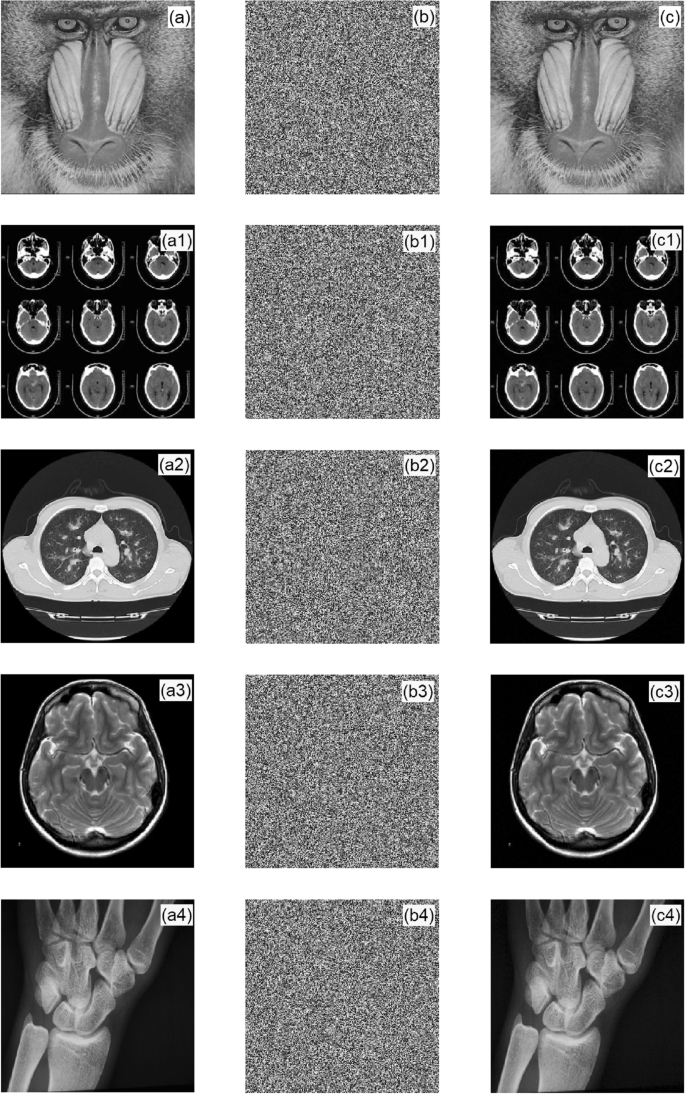

In the simulation experiment, Baboon, brain CT, chest CT, DR film, and MRI gray images were selected, and their pixels were 256 × 256. Figure 6 shows the original image, ciphertext image, and decrypted image.